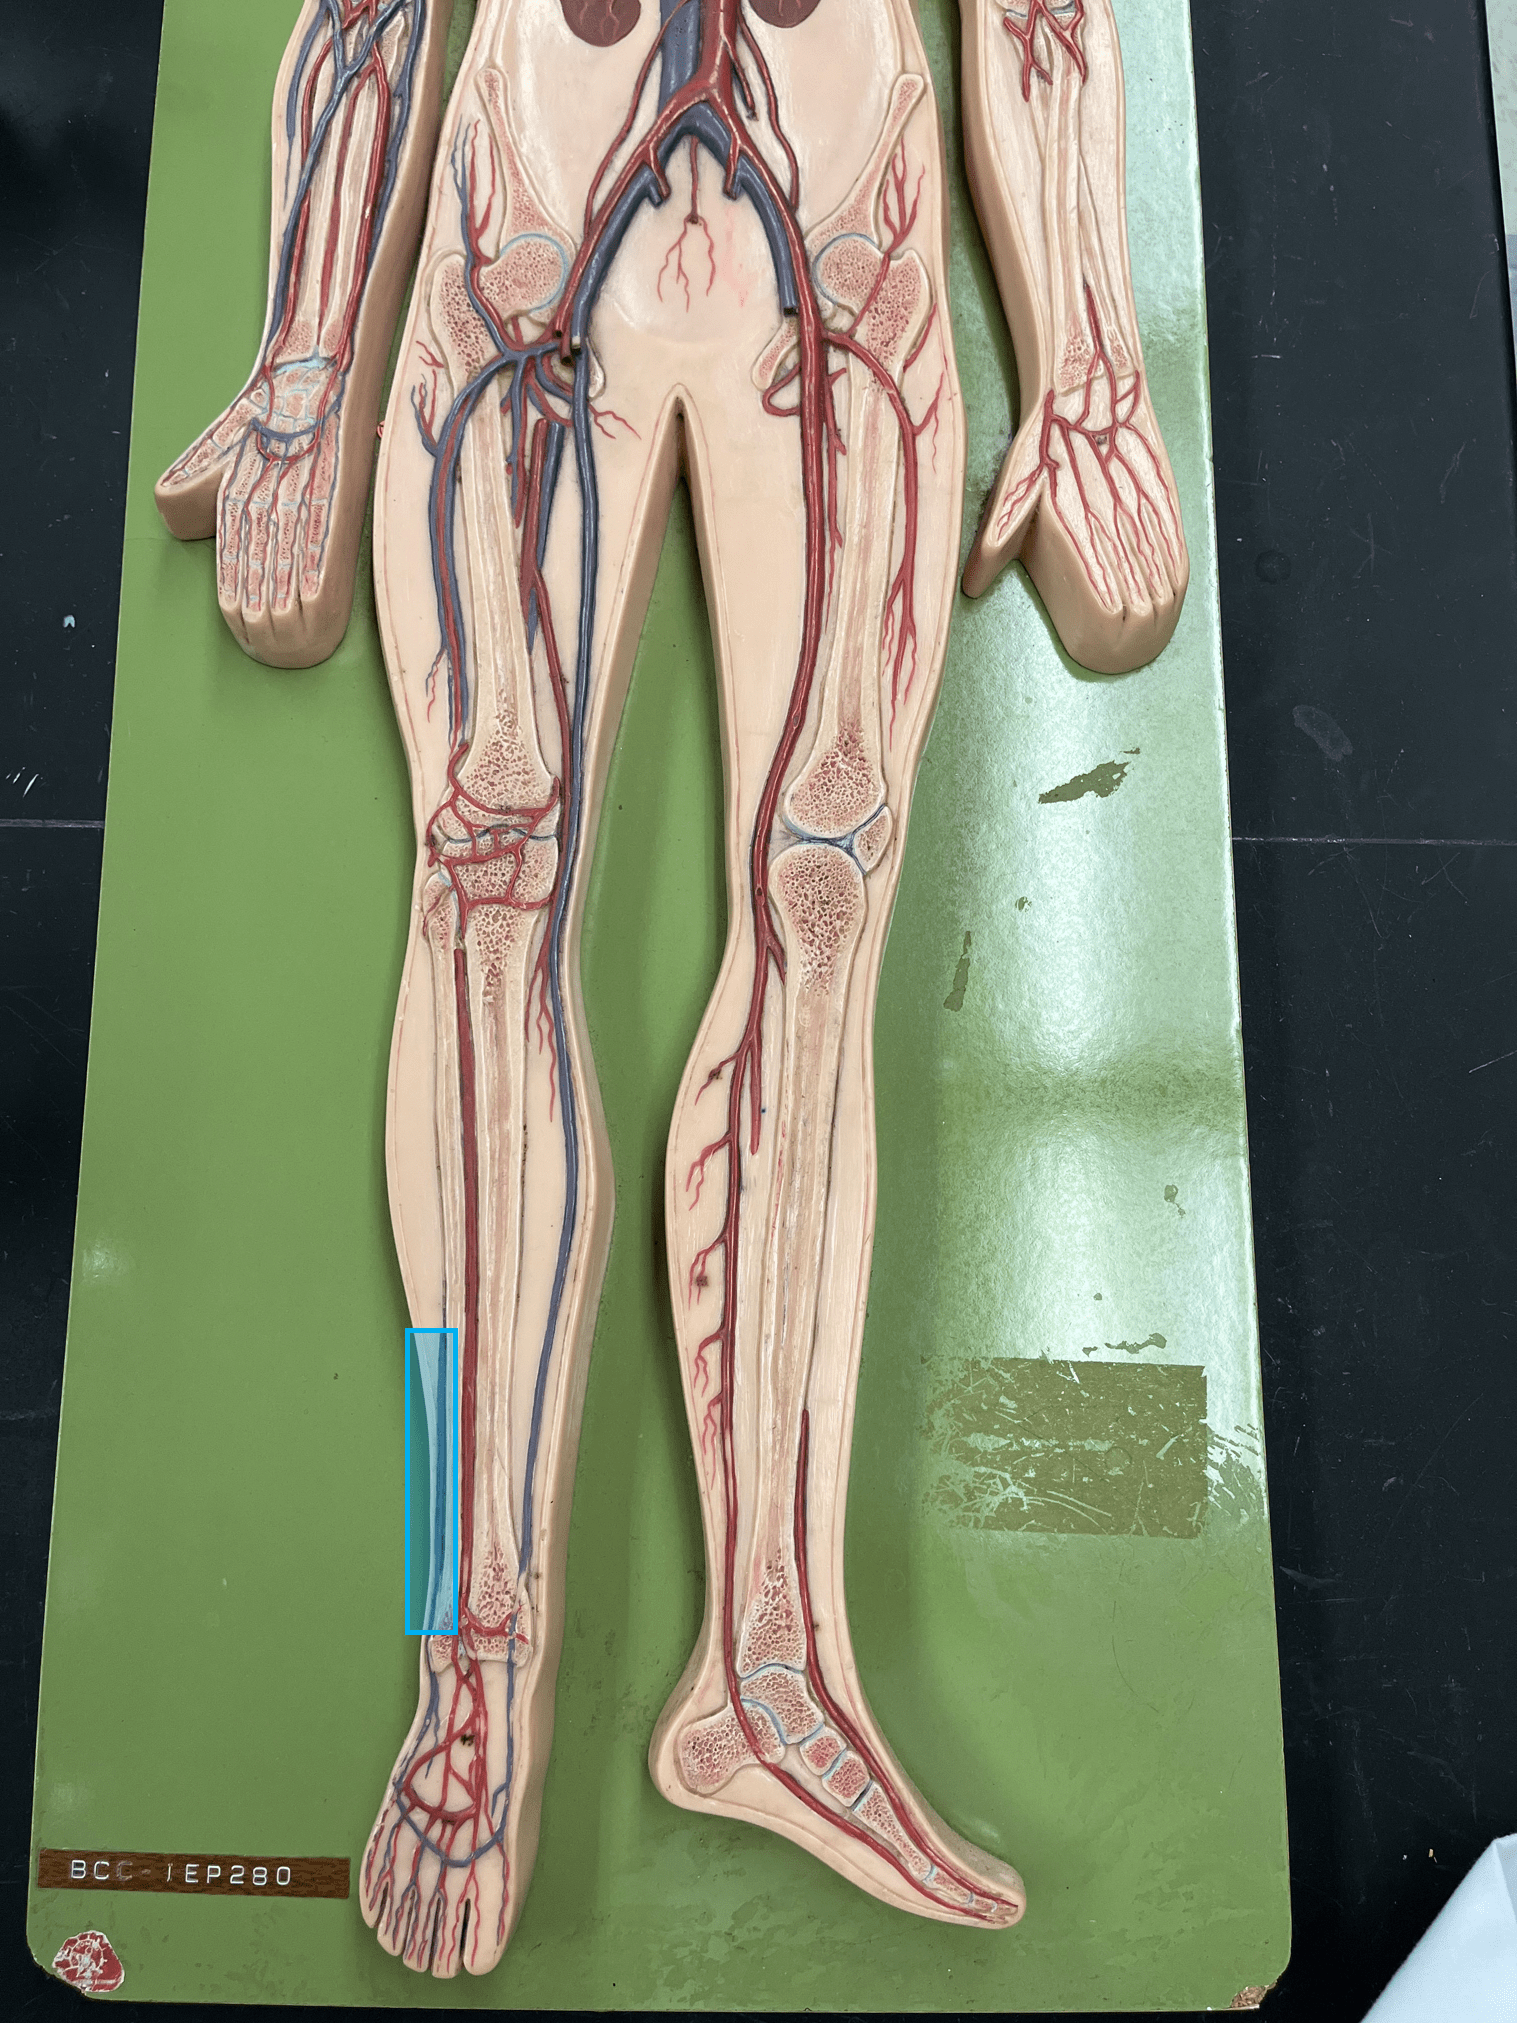

• Establishes unidirectional flow of blood.

• An artery of the head and neck.